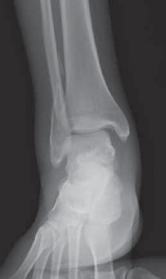

FIG 5 • A. Skin necrosis and slough following surgical intervention. B. CT scan demonstrating fibular nonunion at 6 months following open reduction and A B internal fixation of a pronation–abduction injury. COMPLICATIONS 1. Minor complications include epidermolysis (FIG 5A), superficial infection, and peroneal tendinitis with painful hardware.

2. Major problems include nonunion (

FIG 5B

), hardware fail-

ure, deep infection, and compartment syndrome.**